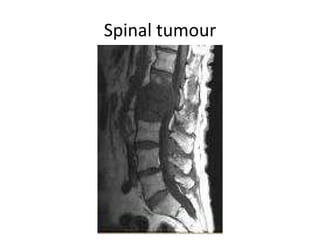

Spinal tumour

Cauda equina syndrome can be caused by anything which compresses the lumbo-sacral nerves  (the cauda equina) Big disc prolapses in young people Tumours which can be primary or metastatic Infection including discitis and spinal abscesses Trauma bone fragments and blood clots Ligamentous hypertrophy in elderly with canal stenosis